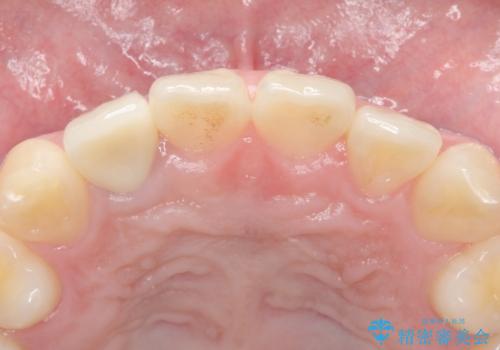

精査したところ、透過性のあるセラミッククラウンで治療されており、内側の黒い土台が透けてクラウンが黒ずんで見えていました。

土台を白いファイバーコアにやりかえたのち、土台の色を透過させないジルコニアフレームを用いたセラミッククラウンによる治療を行いました。